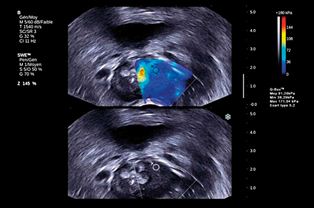

Ultrasound shear waves can be used to measure elasticity in soft tissue and distinguish between healthy tissue and tumours, as shown by the colouring.

Ultrasound creates two types of waves; the most common type is a pressure wave, which penetrates the tissue. The second type, called shear wave, is created by the radiation pressure from the pressure wave and runs horizontally. While pressure waves are mostly affected by fluids, shear waves capture the characteristics of the other 30% of the body that does not consist of water.

Shear waves are created when pressure waves are sent to specific points. From there, the special diagonal energy waves are created. The trick is to use the regular ultrasound waves to measure the diagonal energy pulse.